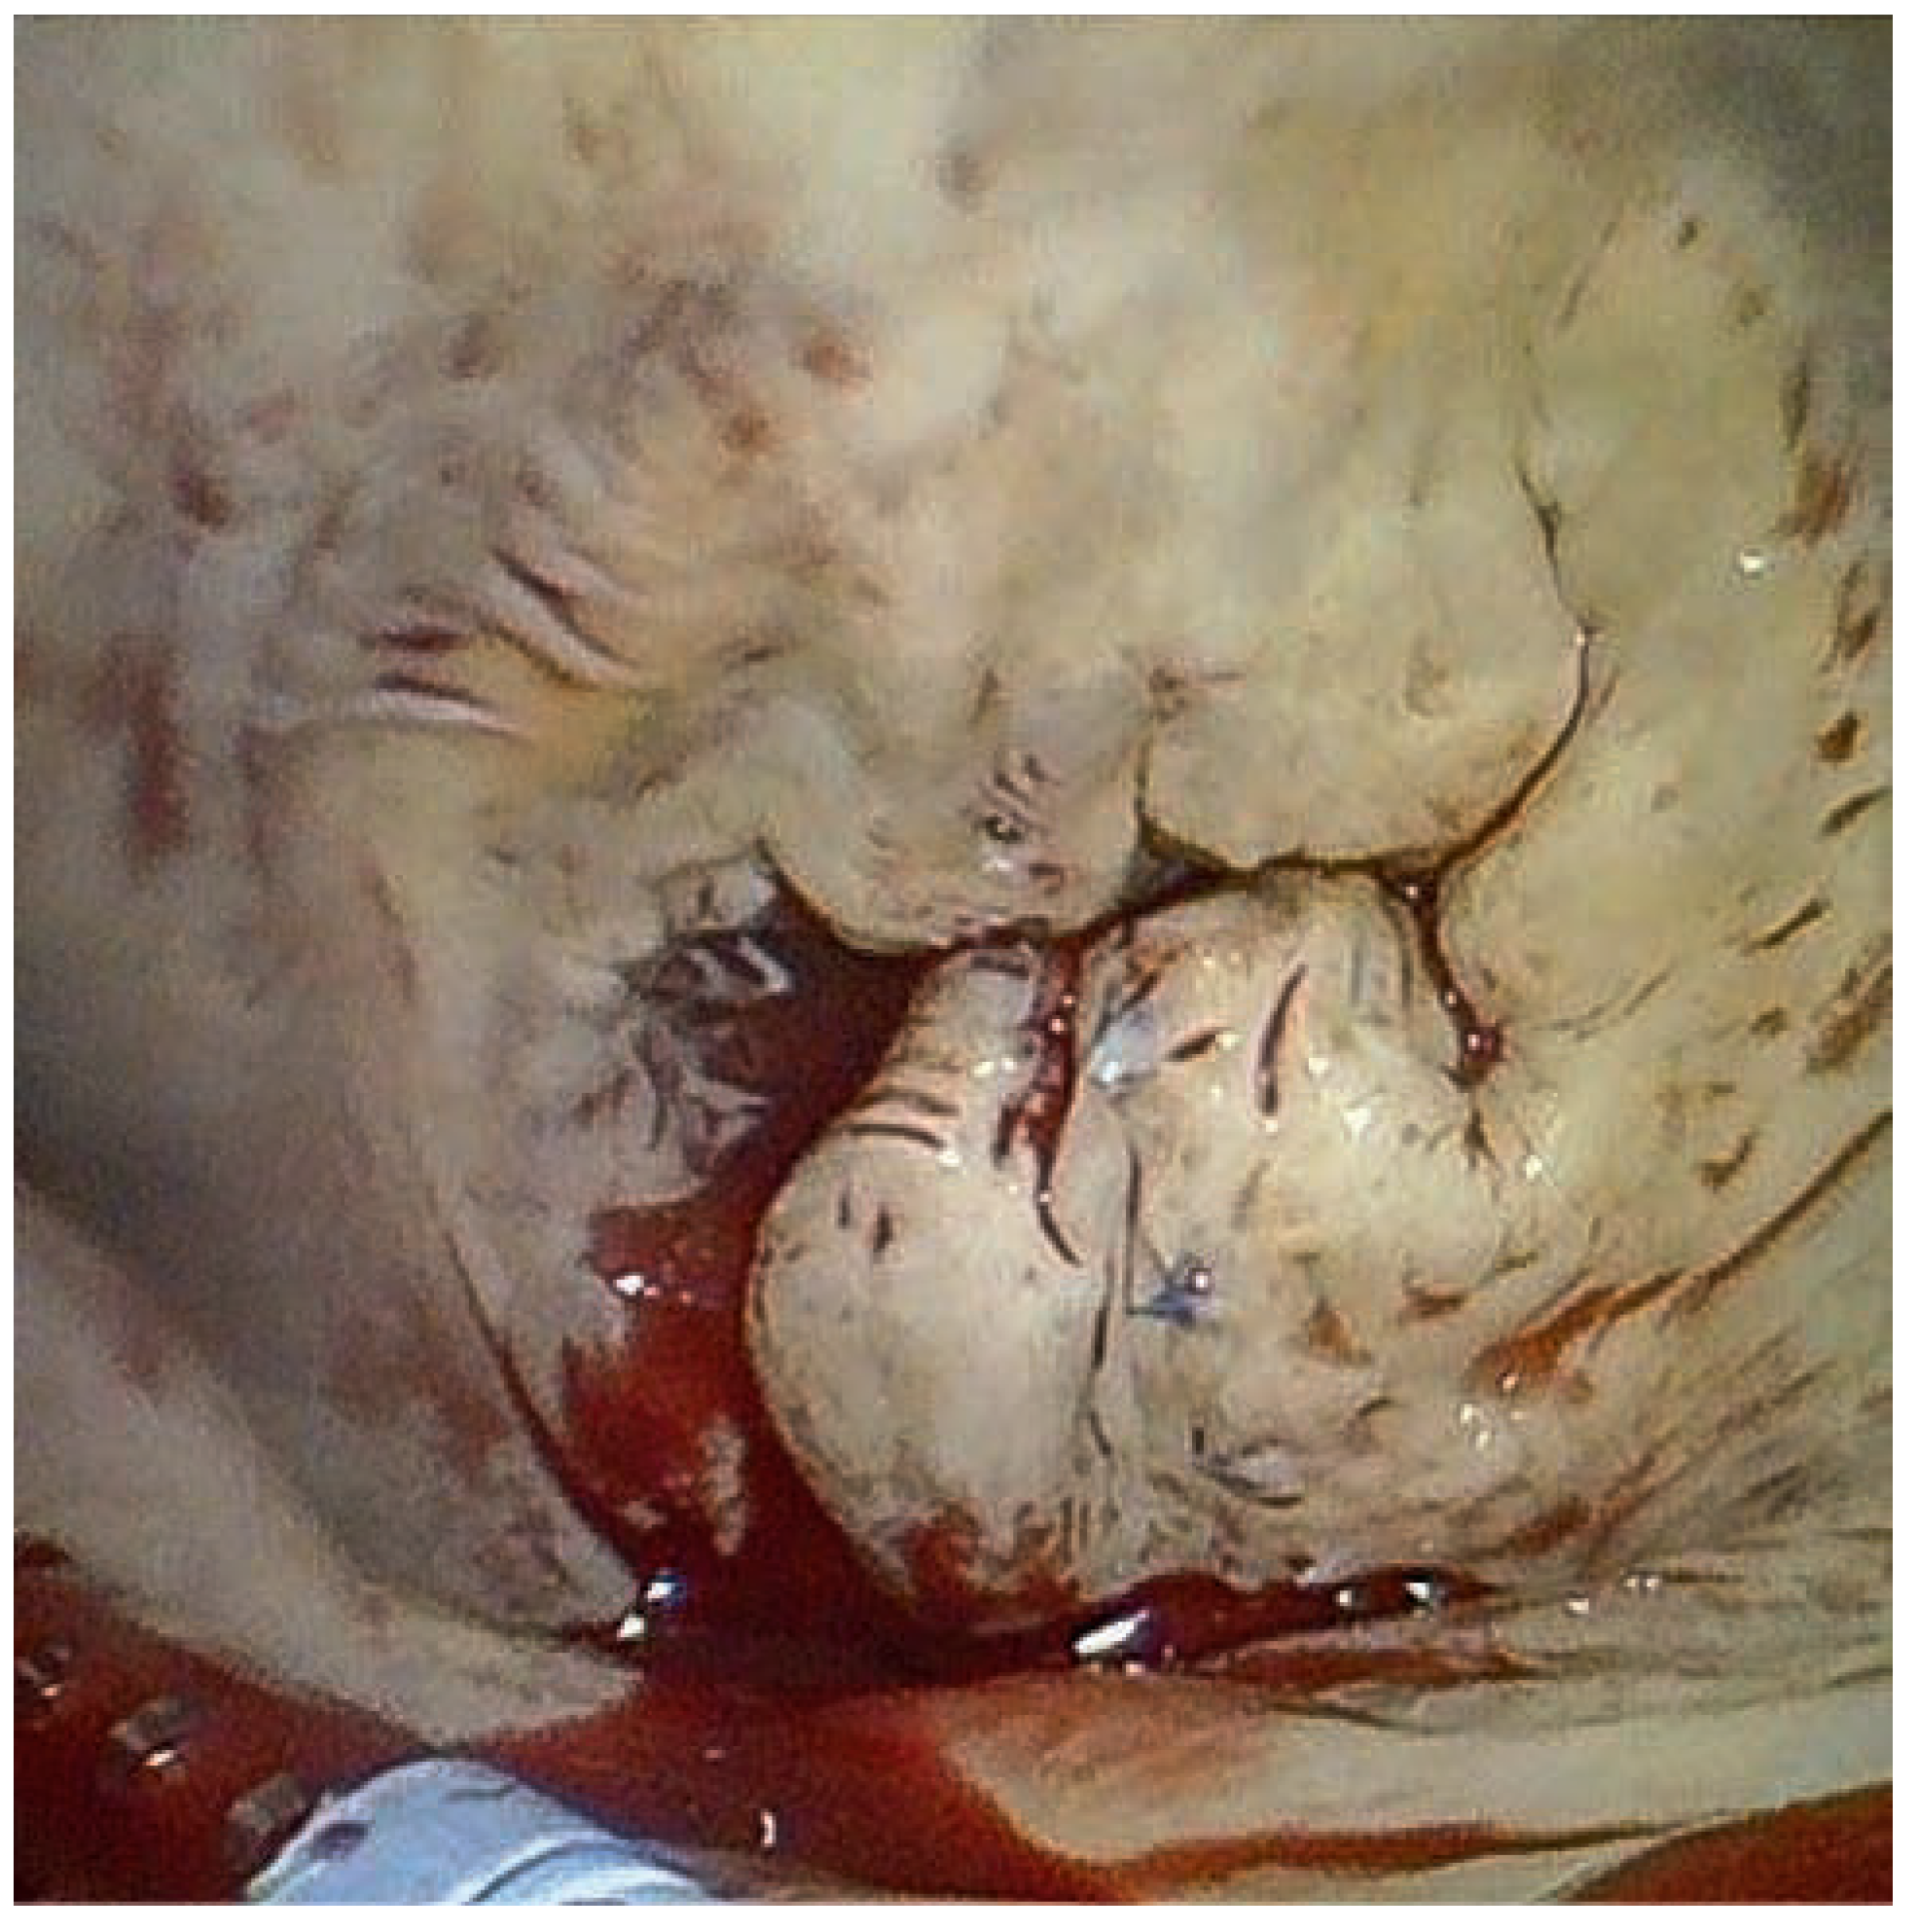

A 59-year-old man was referred to our institution for dyspnea. He had a history of mitral valve regurgitation with posterior leaflet valve prolapse. In 2006 he underwent mitral repair without annuloplasty ring implantation. In April 2012 dyspnea, NYHA II–III, recurred. Echocardiography showed grade III to IV mitral regurgitation. He was referred to another hospital, where percutaneous treatment with MitraClip™ implantation was proposed to the patient. Two MitraClips™ were implanted. Shortly after the intervention the patient complained about shortness of breath. He was seen at our hospital. Transthoracic echocardiography (Figure 1) and cardiac computed tomography (Figure 2) confirmed the clinical impression of both mitral stenosis and regurgitation with significant gradient and a valve surface of 1.7 cm2. M-mode echocardiography showed typical patterns of mitral stenosis (Figure 3). Mitral valve repair with annuloplasty could be performed with neocordals, reinforcement of the posterior leaflet and ring implantation (Figure 4 and Figure 5). Six months later, the mitral valve is fully functional and the patient is asymptomatic. This case is remarkable for a few points: firstly, mitral annuloplasty with ring implantation should be performed instead of simple repair. Secondly, equivalence of surgery with MitraClip™ implantation has been proven in some trials. However patients included in these studies were older and sicker than our patient. There are more arguments to suggest that MitraClip™ should be reserved for nonoperable patients or to patients refusing surgery. In our patient, revision surgery was probably a better option than a percutaneous approach. Valve dysfunction requiring a second intervention is almost 10 times more frequent after MitraClip™ implantation than after conventional surgery. Thirdly, even though trials about MitraClip™ are still ongoing, indications should not be lifted to younger patients, until we have clear evidence regarding the comparison of the 2 techniques. Finally, mitral valve repair with annuloplasty and ring implantation is possible after MitraClip™ implantation.

Figure 5. Final result after mitral valve repair and ring implantation.